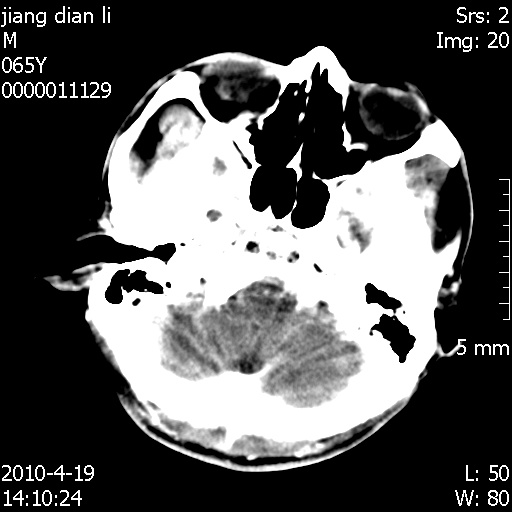

老年男性,突发左下肢无力1天,其余有价值的检查都没有。平扫ct值大约60hu,增强后ct值没什么改变,请大家讨论一下这个病例是什么?说明诊断理由。

左小脑、右大脑顶叶多发圆形高密度病灶,其周环状低密度影。考虑多发脑出血。隔期观察。

考虑转移瘤并出血

多发,考虑转移瘤。不增强,也许是因为缺乏血供 。

至于是出血还是微小钙化所致的高密度无法考证,三个都出血也不是一点都不可能,同一种组织学类型的肿瘤受到同一个外来的因素影响后会表现出相同的病理变化。说实在的,我本身支持转移瘤的,就是想不通为什么不强化?我认为单纯脑出血的边缘不会那么光滑,并且那也不是出血的常见部位,多发也不常见。

刚刚复习了转移瘤的不典型ct征象,有4条,分享给大家:

1、高密度灶:多为瘤内有较多沙粒体钙化所致,而不是出血,ct值可高达95hu;

2、无强化;

3、无水肿;

4、无占位效应。